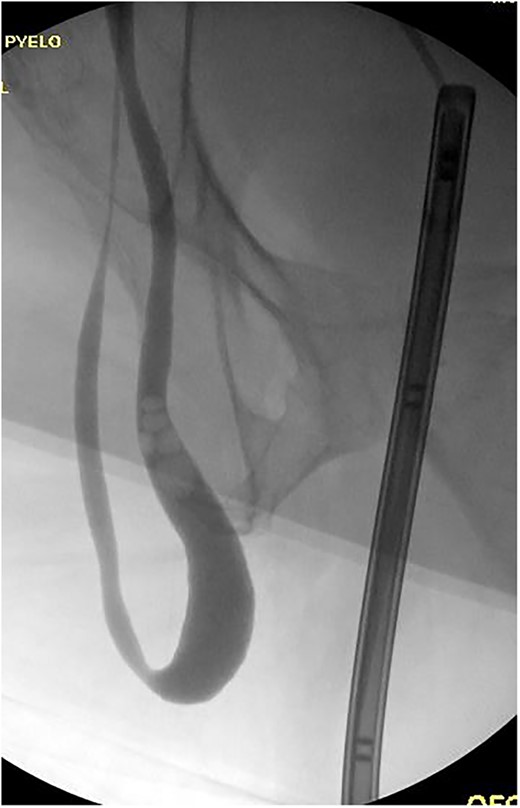

The patient was taken to the operative suite where he underwent cystoscopy, retrograde pyelogram and temporary ureteral stent placement (Fig. 2). Right inguinal exploration was performed, and the patient was found to have a large direct hernia containing abundant adipose tissue. The ureter and cord structures were identified. Adipose tissue was amputated with an energy device. The ureter was reduced into the retroperitoneum. The hernia was then repaired with modified Lichtenstein technique using macroporous polypropylene mesh. Retrograde pyelogram was repeated at completion of the hernia repair following stent removal. A serpiginous course of the ureter was noted without obstruction (Fig. 3). He was observed overnight and discharged home the following day. Post-operative course was uneventful.

Retrograde pyelogram exhibiting ureter herniated into scrotum prior to hernia repair. Filling defects consistent with air bubbles.